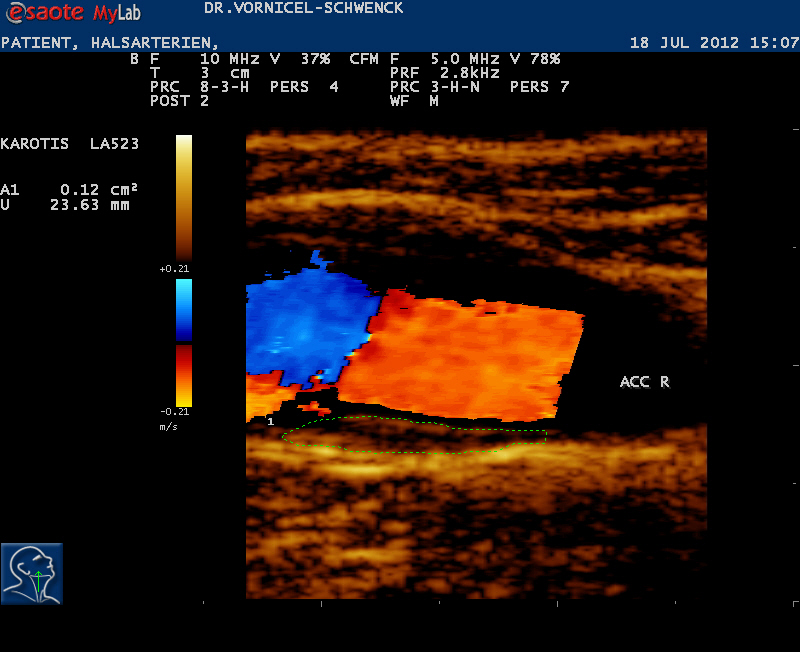

Sonografie (Sonographie), auch Echografie oder umgangssprachlich Ultraschall genannt, ist die Anwendung von Ultraschall als bildgebendes Verfahren zur Untersuchung von organischem Gewebe in der Medizin. Ein Sonogramm ist ein Bild, das mit Hilfe der Sonografie erstellt wurde.

Ein wesentlicher Vorteil liegt in der Unschädlichkeit der eingesetzten Schallwellen. Die Anwendung von Ultraschall ist eine sehr sichere Methode für die Bildgebung.

Die Sonografie ist das wichtigste Verfahren bei der Differentialdiagnose eines Akuten Abdomens, bei Gallensteinen oder bei der Beurteilung von Gefäßen und deren Durchlässigkeit. Sie wird standardmäßig zur Untersuchung der Schilddrüse, des Herzens und der Bauchorgane benutzt. Alle wasserhaltigen, blutreichen Organe sind für den Ultraschall gut untersuchbar. Manche Organe sind im Normalzustand nur schwierig, im krankhaft vergrößerten Zustand dagegen ganz gut erkennbar (Blinddarm, Harnleiter, Nebennieren).